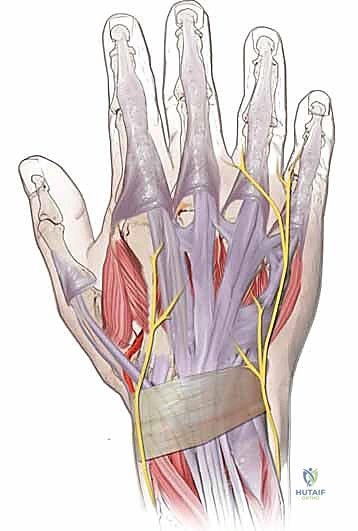

FIG 1 • Tendons on the dorsum of the hand, extensor retinaculum.

The intrinsic muscles (seven interossei and four lumbricals) are vital for the hand's delicate balance. They flex the MP joints and extend the IP joints. On the dorsum of the hand, the juncturae tendinum connect the EDC tendons of the long, ring, and small fingers, allowing for grouped extension. The EIP and EDM, however, provide independent extension.

Distal to the MP joint, the dorsal extensor apparatus forms from both extrinsic and intrinsic contributions. The central slip, a continuation of the extrinsic extensor tendon, inserts into the dorsal base of the middle phalanx. The lateral bands, formed by the intrinsic muscles, contribute to the central slip and combine dorsally over the middle phalanx to form the terminal extensor tendon, inserting on the dorsal base of the distal phalanx. The transverse and oblique retinacular ligaments stabilize these structures.